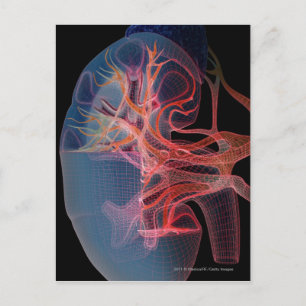

Trådremmar på insidan av en njure vykort

Pris21,00 kr